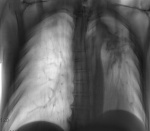

Посмотрим обзор. Красным трахея, желтым главный левый бронх.

Теперь посмотрим томограмму без перечеркиваний.

Как Вы объясните двухконтурность трахеи? Где ее изгиб, явственно видимый на обзорном снимке? И главный вопрос. На одном срезе могут отчетливо контурировся трахея, главные бронхи и ЦЕЛИКОМ НИСХОДЯЩИЙ ОТДЕЛ АОРТЫ, начиная с ее (аорты) дуги. Нет ли такой возможности, что бронхиальная система на представленном срезе "размазана", "не контурируется", "не в срезе", расположена кпереди от данного среза?

Далее идем, обозначу границы CV, которые на мой взгляд имеют место быть бирюзовым цветом, а границы, расположенного внути синим.

Теперь учитывая расположение трахеи и главных бронхов на обзорном снимке сложим картинку вместе. Красным отмечены предполагаемые границы трахеи, желтым - левого главного бронха, черным обозначен нисходящий отдел аорты, который плавно переходит в дугу, которая "размазана", поскольку лежит за пределами среза, к переди.

Ах, Валентин Львович! Я не просто сомневаюсь. Я вижу, что "мицетома" состоит из пуговицы аорты и деформированного корня лёгкого, смещённого вместе с ней вверх и влево. А нижняя граница "CV" идёт по верхне-наружному контуру пресловутой "мицетомы". Но кто же слушает Миргалину? Такое ощущение, что я тут с ёжиками общаюсь- сплошные иголки в мой адрес. Надеюсь, что Николас нам нарисует.Я бы с радостью, но нет возможности. Могу, конечно на бумаге нарисовать и показать, но желающих поучаствовать

Ах, Валентин Львович! Я не просто сомневаюсь. Я вижу, что "мицетома" состоит из пуговицы аорты и деформированного корня лёгкого, смещённого вместе с ней вверх и влево. А нижняя граница "CV" идёт по верхне-наружному контуру пресловутой "мицетомы".